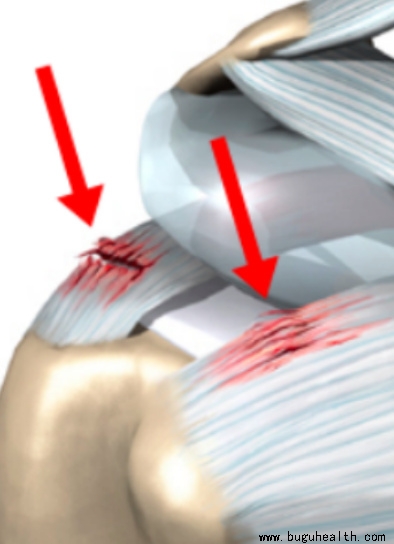

- �ܶ��˶�������粿��ʹ��ͨ�����Ϊ�������ˣ������Լ���û�����ˣ�������������Ϊʲô����������ˣ��������˶���Ҫ���������𣿼���������һ�ֳ����ļ粿������ʹ���������������Ŀ鼡��ļ�����֯���ֱ������ǵĸ��ϼ������¼���СԲ���ͼ����¼������·�������һ������ס���ǵ��Ź�ͷ���ص㸺���ؽ����˶��е��ȶ�.....